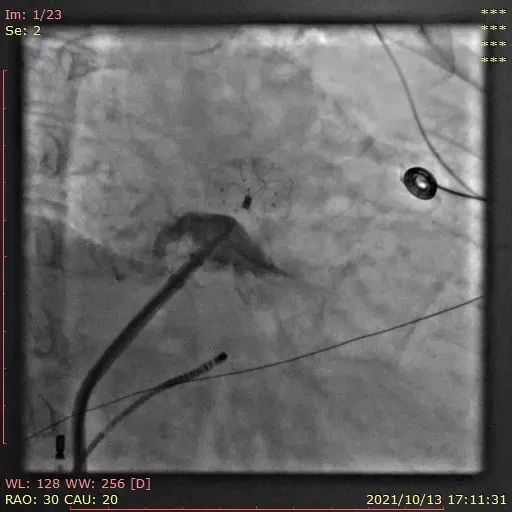

行左心耳头位和足位造影,造影显示左心耳为菜花型。锚定区约为20mm,开口区约为24mm,依据选型原则,拟选LAmbre™2228封堵器或2430封堵器。

图1:RAO30° CRA20° 头位造影

图2:RAO30° CAU20° 足位造影

图3:DSA测量图

综合考虑以上2种型号的利弊和心耳的实际情况,李岳春教授选择LAmbre™2430封堵器并采用 “推送式”植入法打开封堵器,口部半打开固定盘,整体推送到达理想区域后再完全展开固定盘。切线位观察固定盘U型钩与连接件位于同一直线上,且受力均匀,形态良好。

图4:固定盘口部半展开

图5:推送固定盘到理想区域后完全打开

完全展开封堵器后评估:封堵盘此时置于嵴内,不符合预期。李教授通过牵拉操作,使封堵盘成功盖在嵴外,且固定盘锚定良好,非常稳定。释放后再次评估,超声及造影证实封堵器恰能完全覆盖心耳,满足COST原则,结束手术。

图6:DSA下牵拉测试图

图7:DSA评估图